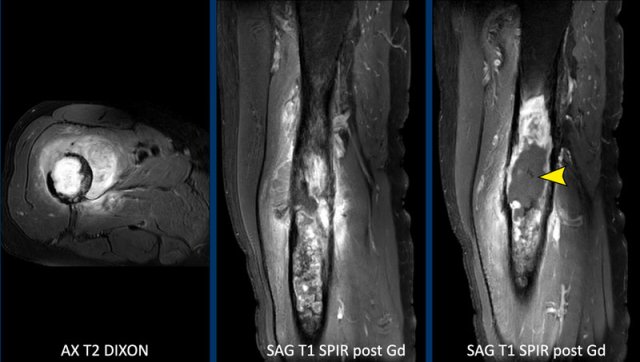

Case

First look at the images.

Then continue reading.

Images

MRI confirms the chondroid nature of the tumor with hyperintense

cartilage nodules on T2 DIXON that show septonodular enhancement after

contrast.

However, there is also marked bone marrow oedema proximally (black arrow) and a periosteal reaction with enhancement (white arrow).

Conclusion

These features are very suspicious for the diagnosis of a high

grade chondrosarcoma.

Axial T1 weighted image confirms deep

anterior cortical scalloping over approximately 1/3 of the cortex, i.e. extensive scalloping ( > 10% of tumor circumference).

A proximal femur resection

was performed.

Final diagnosis: chondrosarcoma grade II